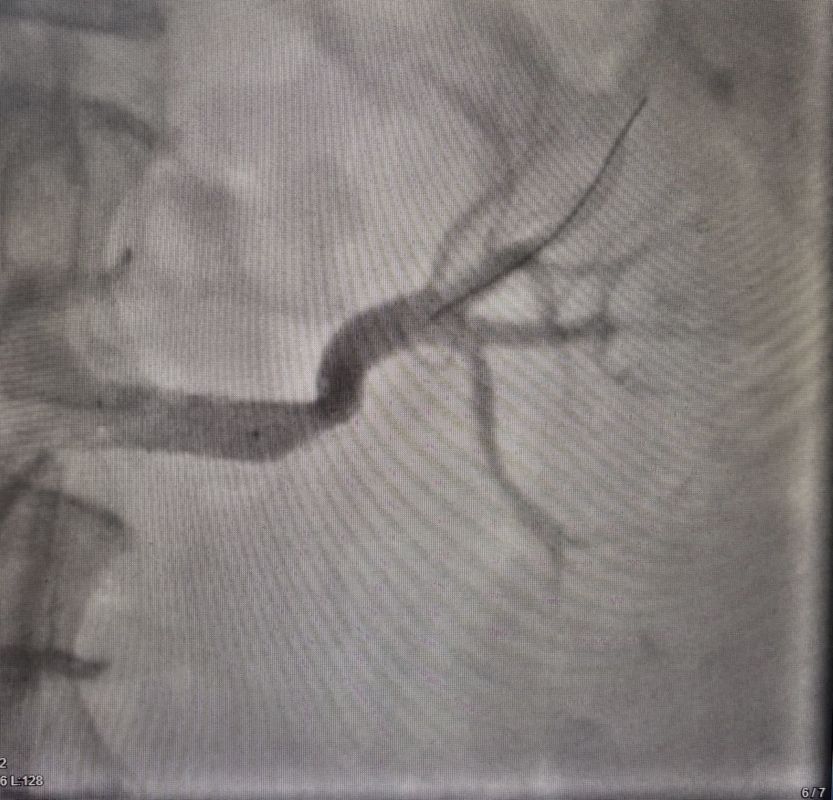

Врачи обследовали женщину и диагностировали критический стеноз — патологическое сужение левой почечной артерии, из-за чего и возникали проблемы с давлением. Лечение показало сужение артерии на 80%.

В ходе операции врачи расширили артерию и установили специальный стент. Давление пациентки стабилизировалось. Спустя год женщина прошла осмотр. Она чувствует себя хорошо.